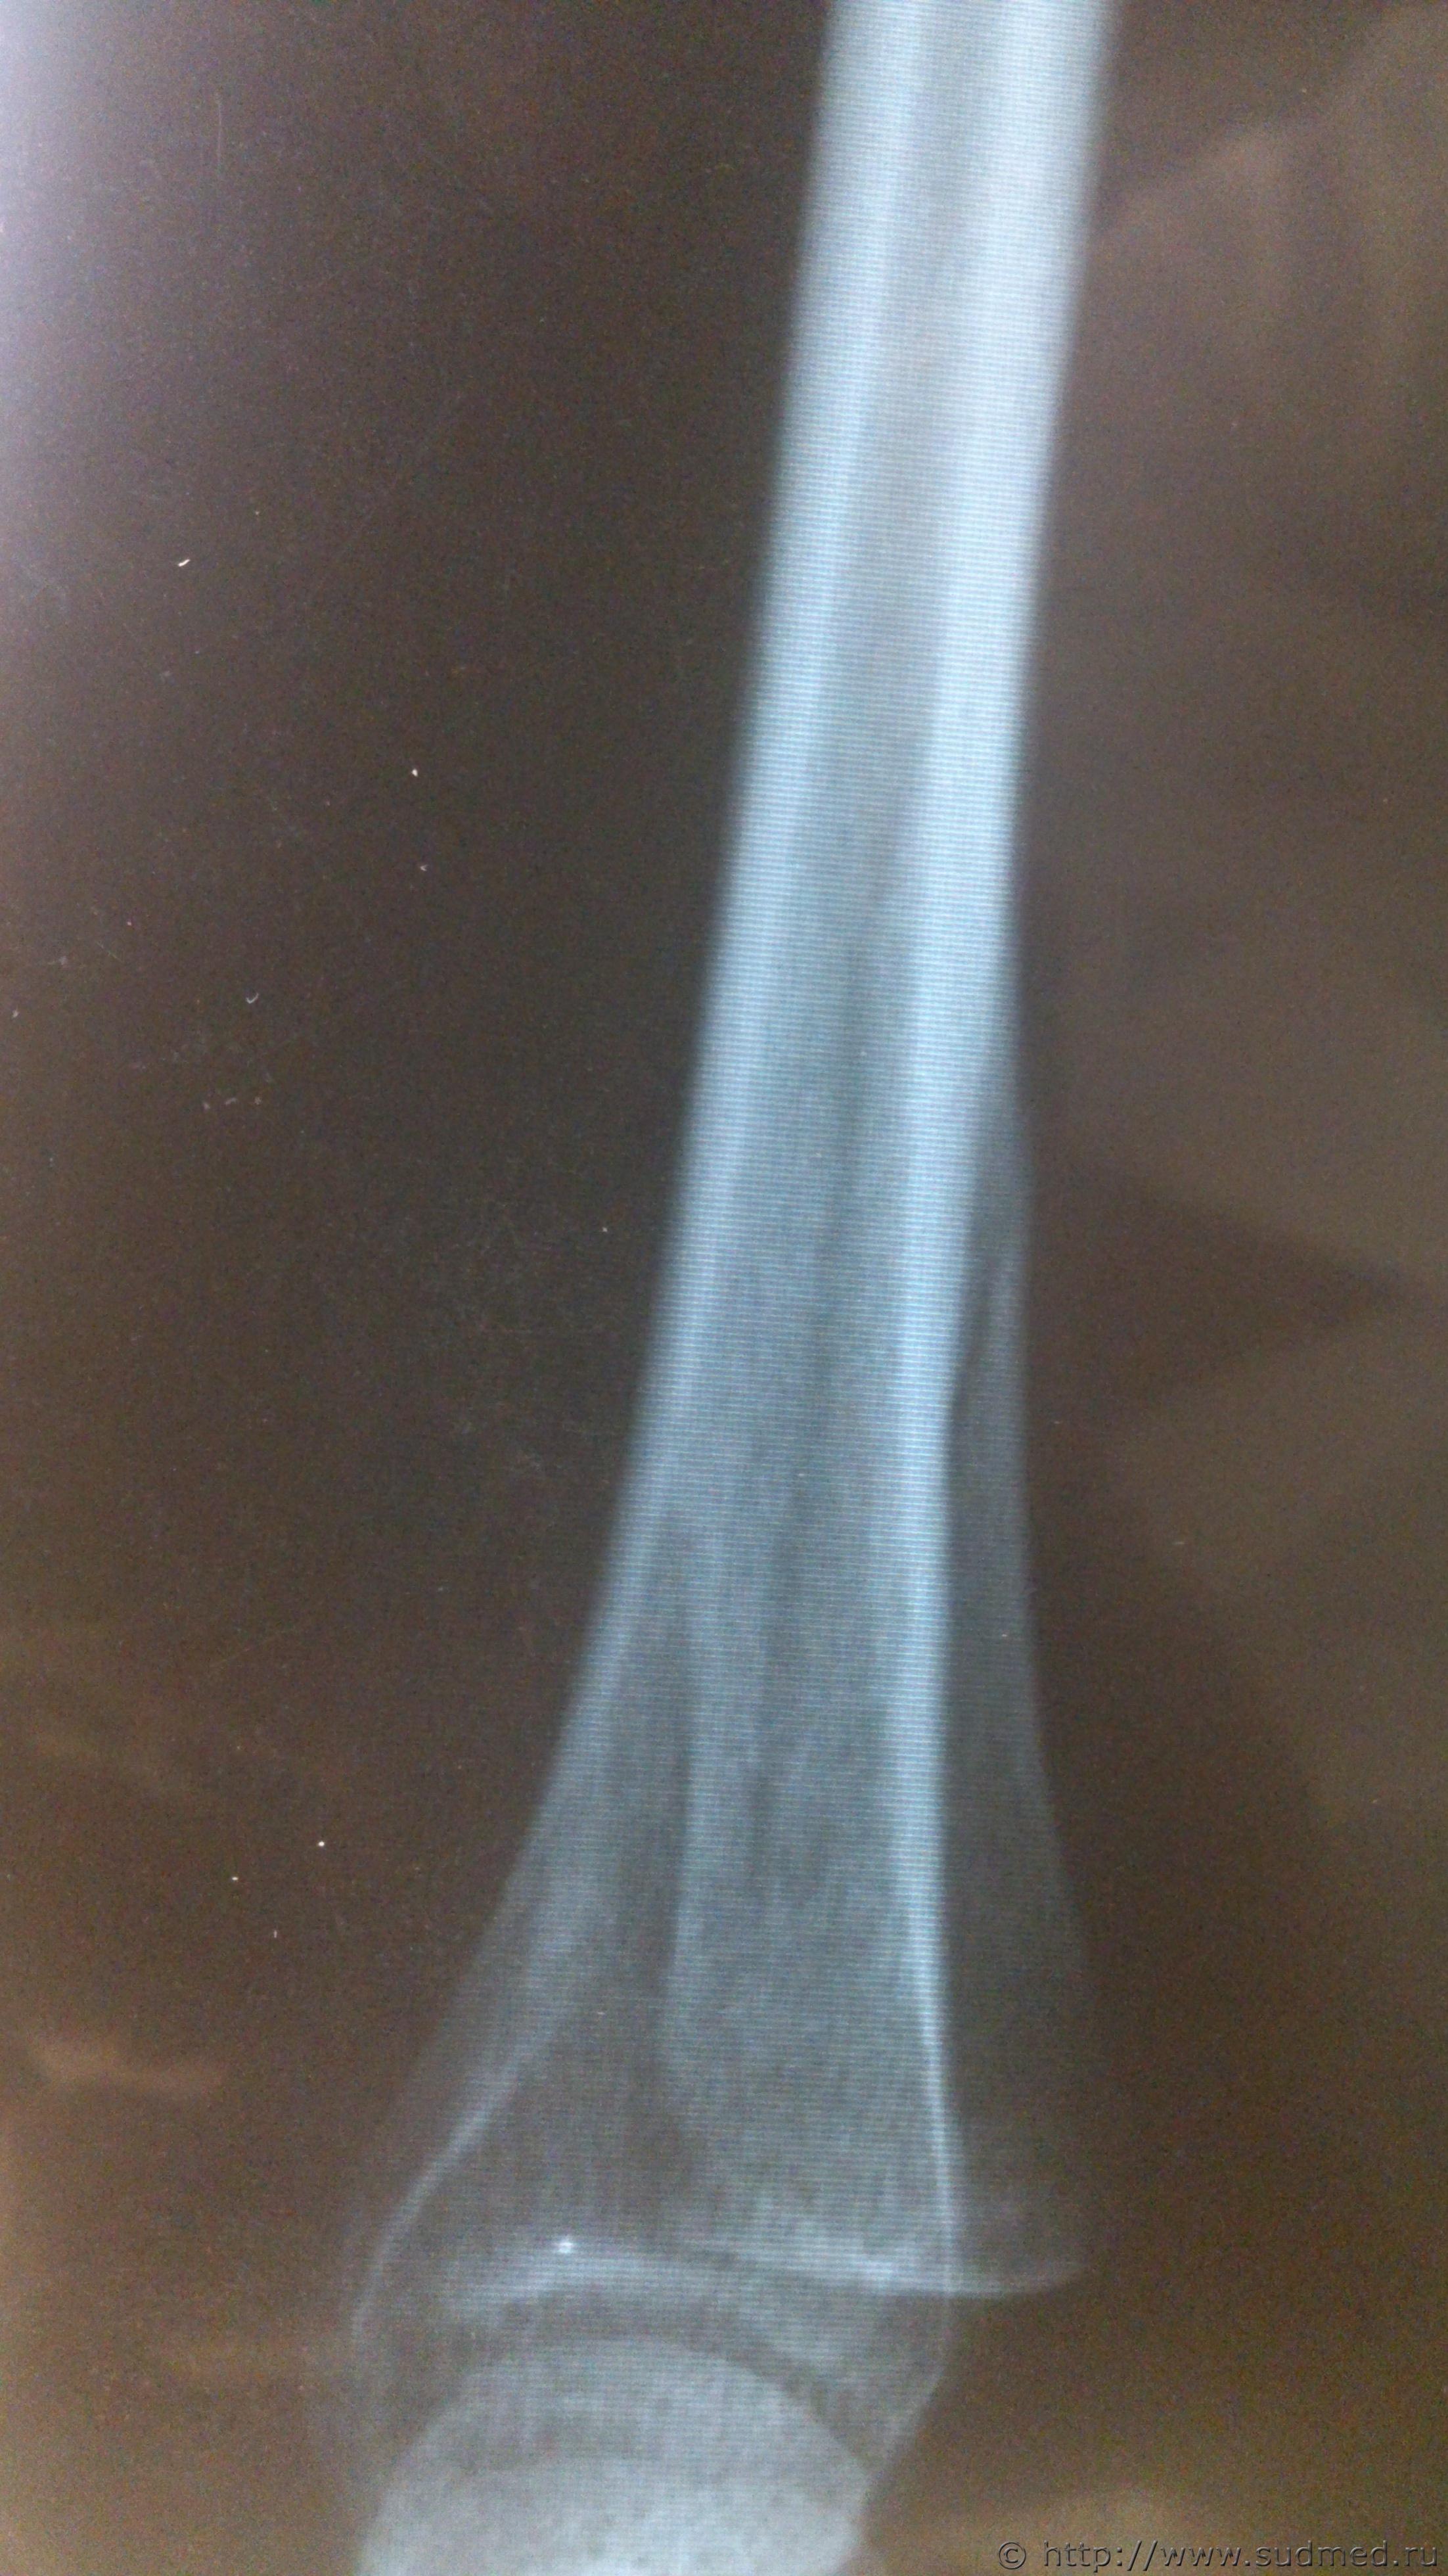

Здравствуйте, уважаемые коллеги! Возник вопрос по механизму образования перелома локтевой кости. Согласно описанию рентгенолога: «в нижней трети правой локтевой кости определяются два линейных просветления, направленных параллельно оси кости, шириной около 2,0 мм, с достаточно четкими контурами, без деформации оси кости, без видимой динамики рентгенологической картины между исследованиями (от 01.09.16 и от 07.10.16) – признаки консолидации не выявляются (отсутствует уплотнение костной структуры, костная мозоль не формируется)» Выводы: установлены признаки вертикального перелома правой локтевой кости в нижней трети без смещения отломков. Диагноз травмпункта: «Закрытый перелом ДМЭ правой локтевой кости со смещением отломков». По обстоятельствам - «нанес один удар деревянным стулом сверху-вниз, защищаясь от удара, лежа на кровати, подставила свою правую руку». Встречался ли кто-нибудь с такого рода переломами и есть ли соображения относительно механизма его образования.

Эскизы прикрепленных изображений

Судебная медицина - Прикрепленное изображение Судебная медицина - Прикрепленное изображение Судебная медицина - Прикрепленное изображение Судебная медицина - Прикрепленное изображение